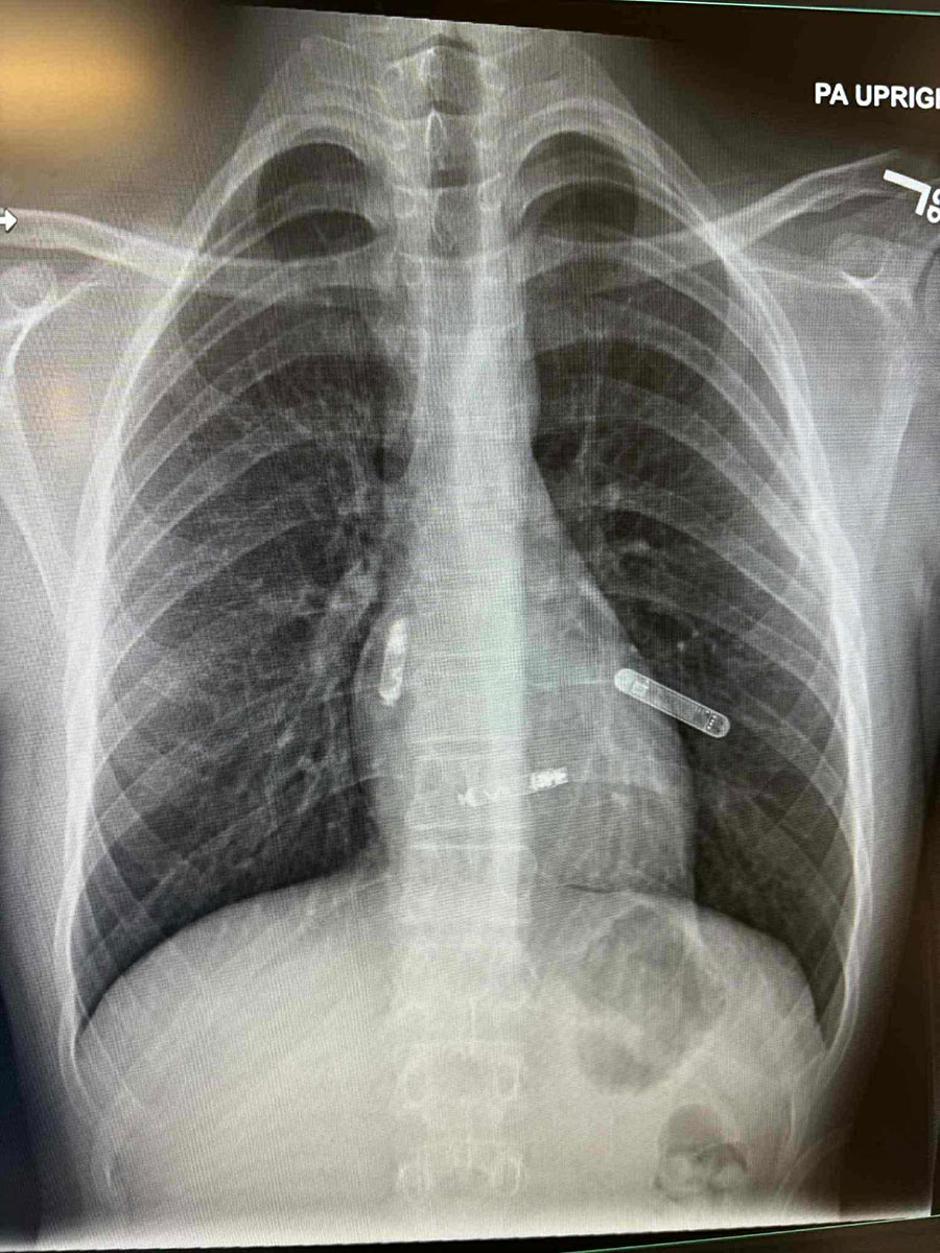

Mostarka dr. Svjetlana Tišma-Dupanović, kardiologinja i pedijatrica, uspješno je pacijentu ugradila dvokomorni pacemaker izravno u srčane šupljine, u pretklijetku i klijetku, koji sinkronizirano potiču pravilan rad srca. Ovo je prva takva operacija izvedena na Floridi i ujedno predstavlja veliki napredak u liječenju srčanih bolesti, osobito kod pacijenata s poremećajima srčanog ritma i oslabljenom pumpnom funkcijom srca.

Tradicionalni pacemakeri postavljaju se ispod kože prsnog koša, a žice prolaze kroz vene do srcaNova tehnologija, koju je primijenila dr. Svjetlana Tišma-Dupanović, omogućuje izravnu ugradnju uređaja unutar srca, bez žica koje prolaze kroz krvne žile.

Ovaj dvokomorni (biventrikularni) pacemaker sinkronizira rad pretklijetki i klijetki, čime se postiže pravilniji ritam i učinkovitije pumpanje krvi, objavio je dr. Edhem Čustović na svojoj Facebook stranici, prenosi Jabuka.tv.